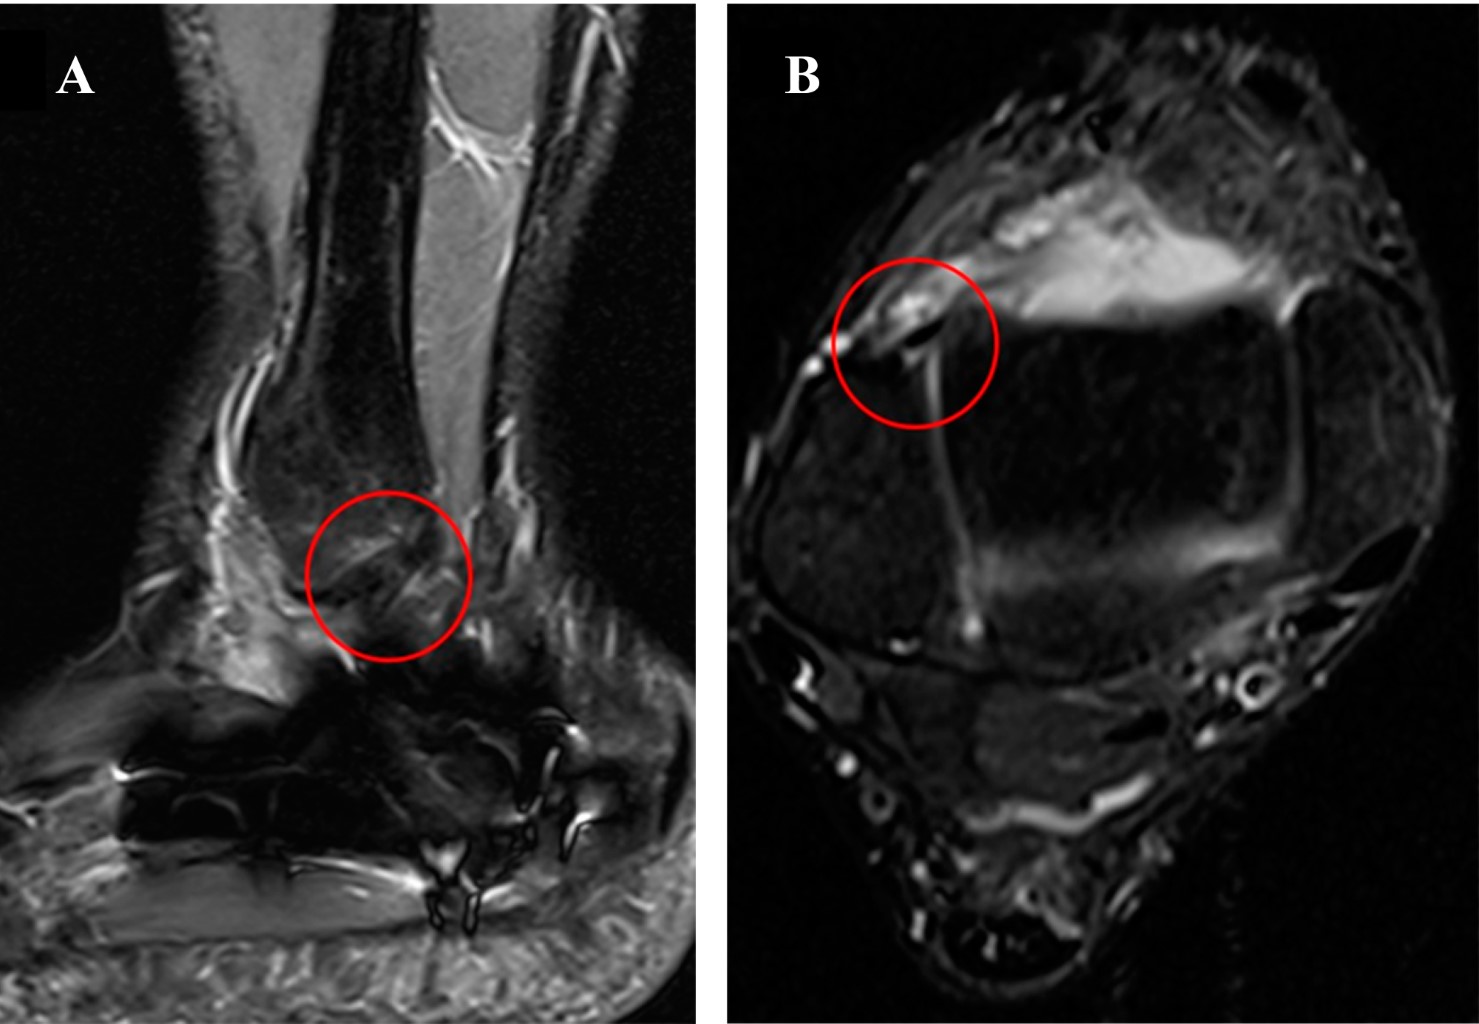

Se evaluó mediante el uso de un goniómetro y un dinamómetro la movilidad y la fuerza del miembro afectado y se la comparó con el lado sano a los 24 meses postoperatorios. El paciente recuperó su rango de movilidad y fuerza. Presentó dolor de 0/10 según la escala visual análoga (EVA). El puntaje según la American Orthopedics Foot and Ankle Society (AOFAS) fue de 92. La resonancia magnética nuclear (RMN) control mostró integridad y continuidad del espesor de ambos ligamentos (Figura 5).

Para el diagnóstico de estas lesiones es necesario realizar radiografías y tomografía computarizada.1,7,10,11 La RMN es superior para observar tejidos blandos por su mejor resolución.7 En la RMN las estructuras ligamentarias se visualizan como bandas de baja intensidad, bien definidas, homogéneas, acentuadas por la grasa periférica. Áreas heterogéneas indican rupturas parciales y las lesiones completas se aprecian como ausencia del ligamento reemplazado por líquido o tejido graso.7,12,13,14,15

Figura 5